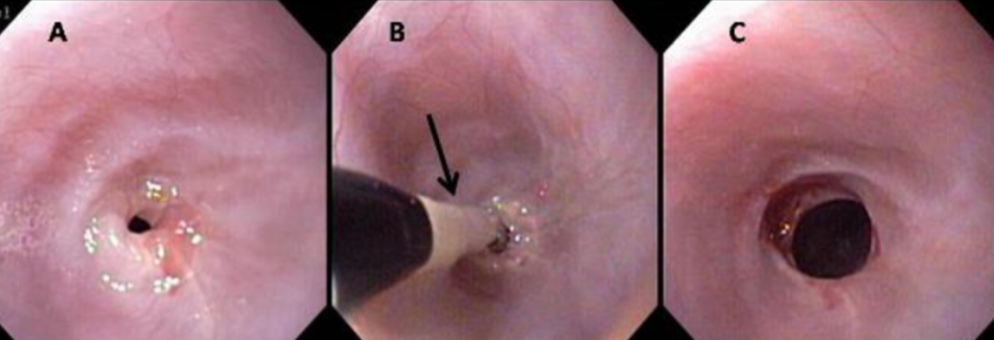

how is esophagitis diagnosed?

-radiographs and contrast studies are usually normal

-endoscopy is most sensitive method but rarely performed unless chronic

how are esophageal strictures diagnosed?

-contrast esophogram (rads or fluoroscopy)

-endoscopy

what is the treatment for esophageal strictures?

-endoscopic balloon dilation (2-3 tx's usually required, up to 5+, every 2-14 days)